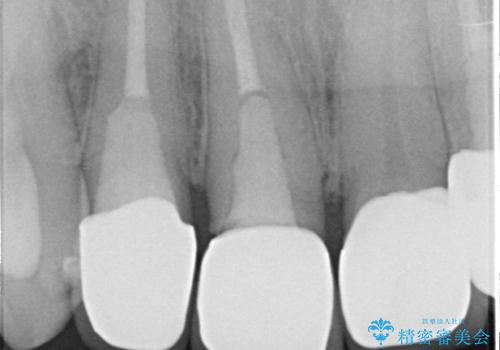

- 右上の前歯が土台ごと外れたといらっしゃった方の症例です。

ファイバーコアという土台から建て直し、咬み合わせに十分注意した上で、オールセラミッククラウンによる補綴を行いました

- オールセラミッククラウン…¥100,000、仮歯…¥10,000、ファイバーコア…¥20,000費用は治療当時の料金となります